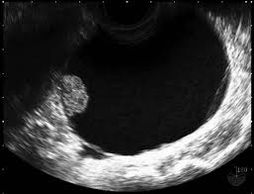

Ectopic pregnancy occurs when the pregnancy is located outside the normal location within the uterus, usually within the fallopian tube. Spotting or bleeding is often the first symptom but patients may also have pain or develop pain later. Most cases of ectopic pregnancy do not require surgery, but can be treated medically with methotrexate.